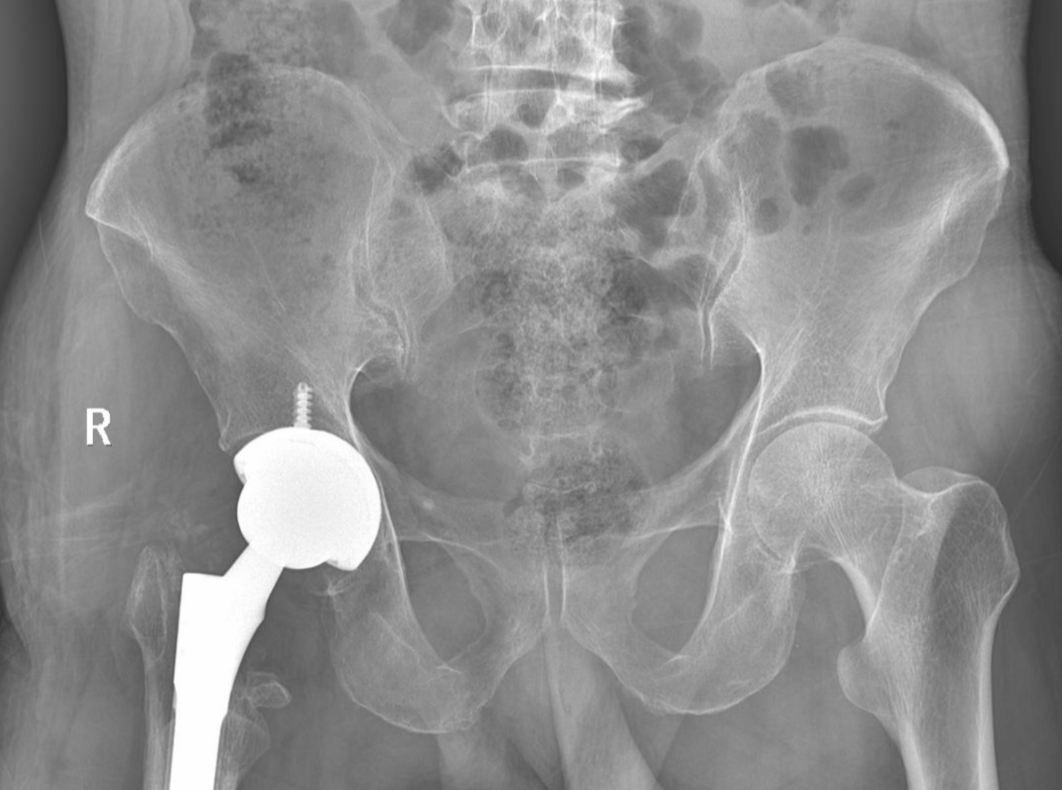

對大家來說,行走是件小事,但對王先生來說是一件難事,原因是62歲的王先生于2024年4月份因干活時不慎摔傷致右髖部疼痛伴活動受限,在外院拍片示“右股骨粗隆間骨折”,并行手術(shù)治療,現(xiàn)患者術(shù)后10月,無法正常下地行走,遂即到我院就診,經(jīng)門診以“右側(cè)股骨頭缺血性壞死、右股骨粗隆間骨折延遲愈合、右股骨粗隆間骨折術(shù)后”收住我科。

術(shù)前:

入院后,科主任魏國華帶領(lǐng)關(guān)節(jié)骨科醫(yī)護(hù)團(tuán)隊積極完善相關(guān)檢查,充分發(fā)揮中醫(yī)骨傷的治療優(yōu)勢,做好充分術(shù)前準(zhǔn)備,根據(jù)患者病情科學(xué)制定個性化治療方案,排除手術(shù)禁忌癥后行右側(cè)PFNA內(nèi)固定取出+右側(cè)人工全髖關(guān)節(jié)置換術(shù),術(shù)程順利,在醫(yī)護(hù)人員的精心治療和護(hù)理下,患者術(shù)后第二天即可扶助行器下地行走,現(xiàn)恢復(fù)良好,已出院。

術(shù)后: